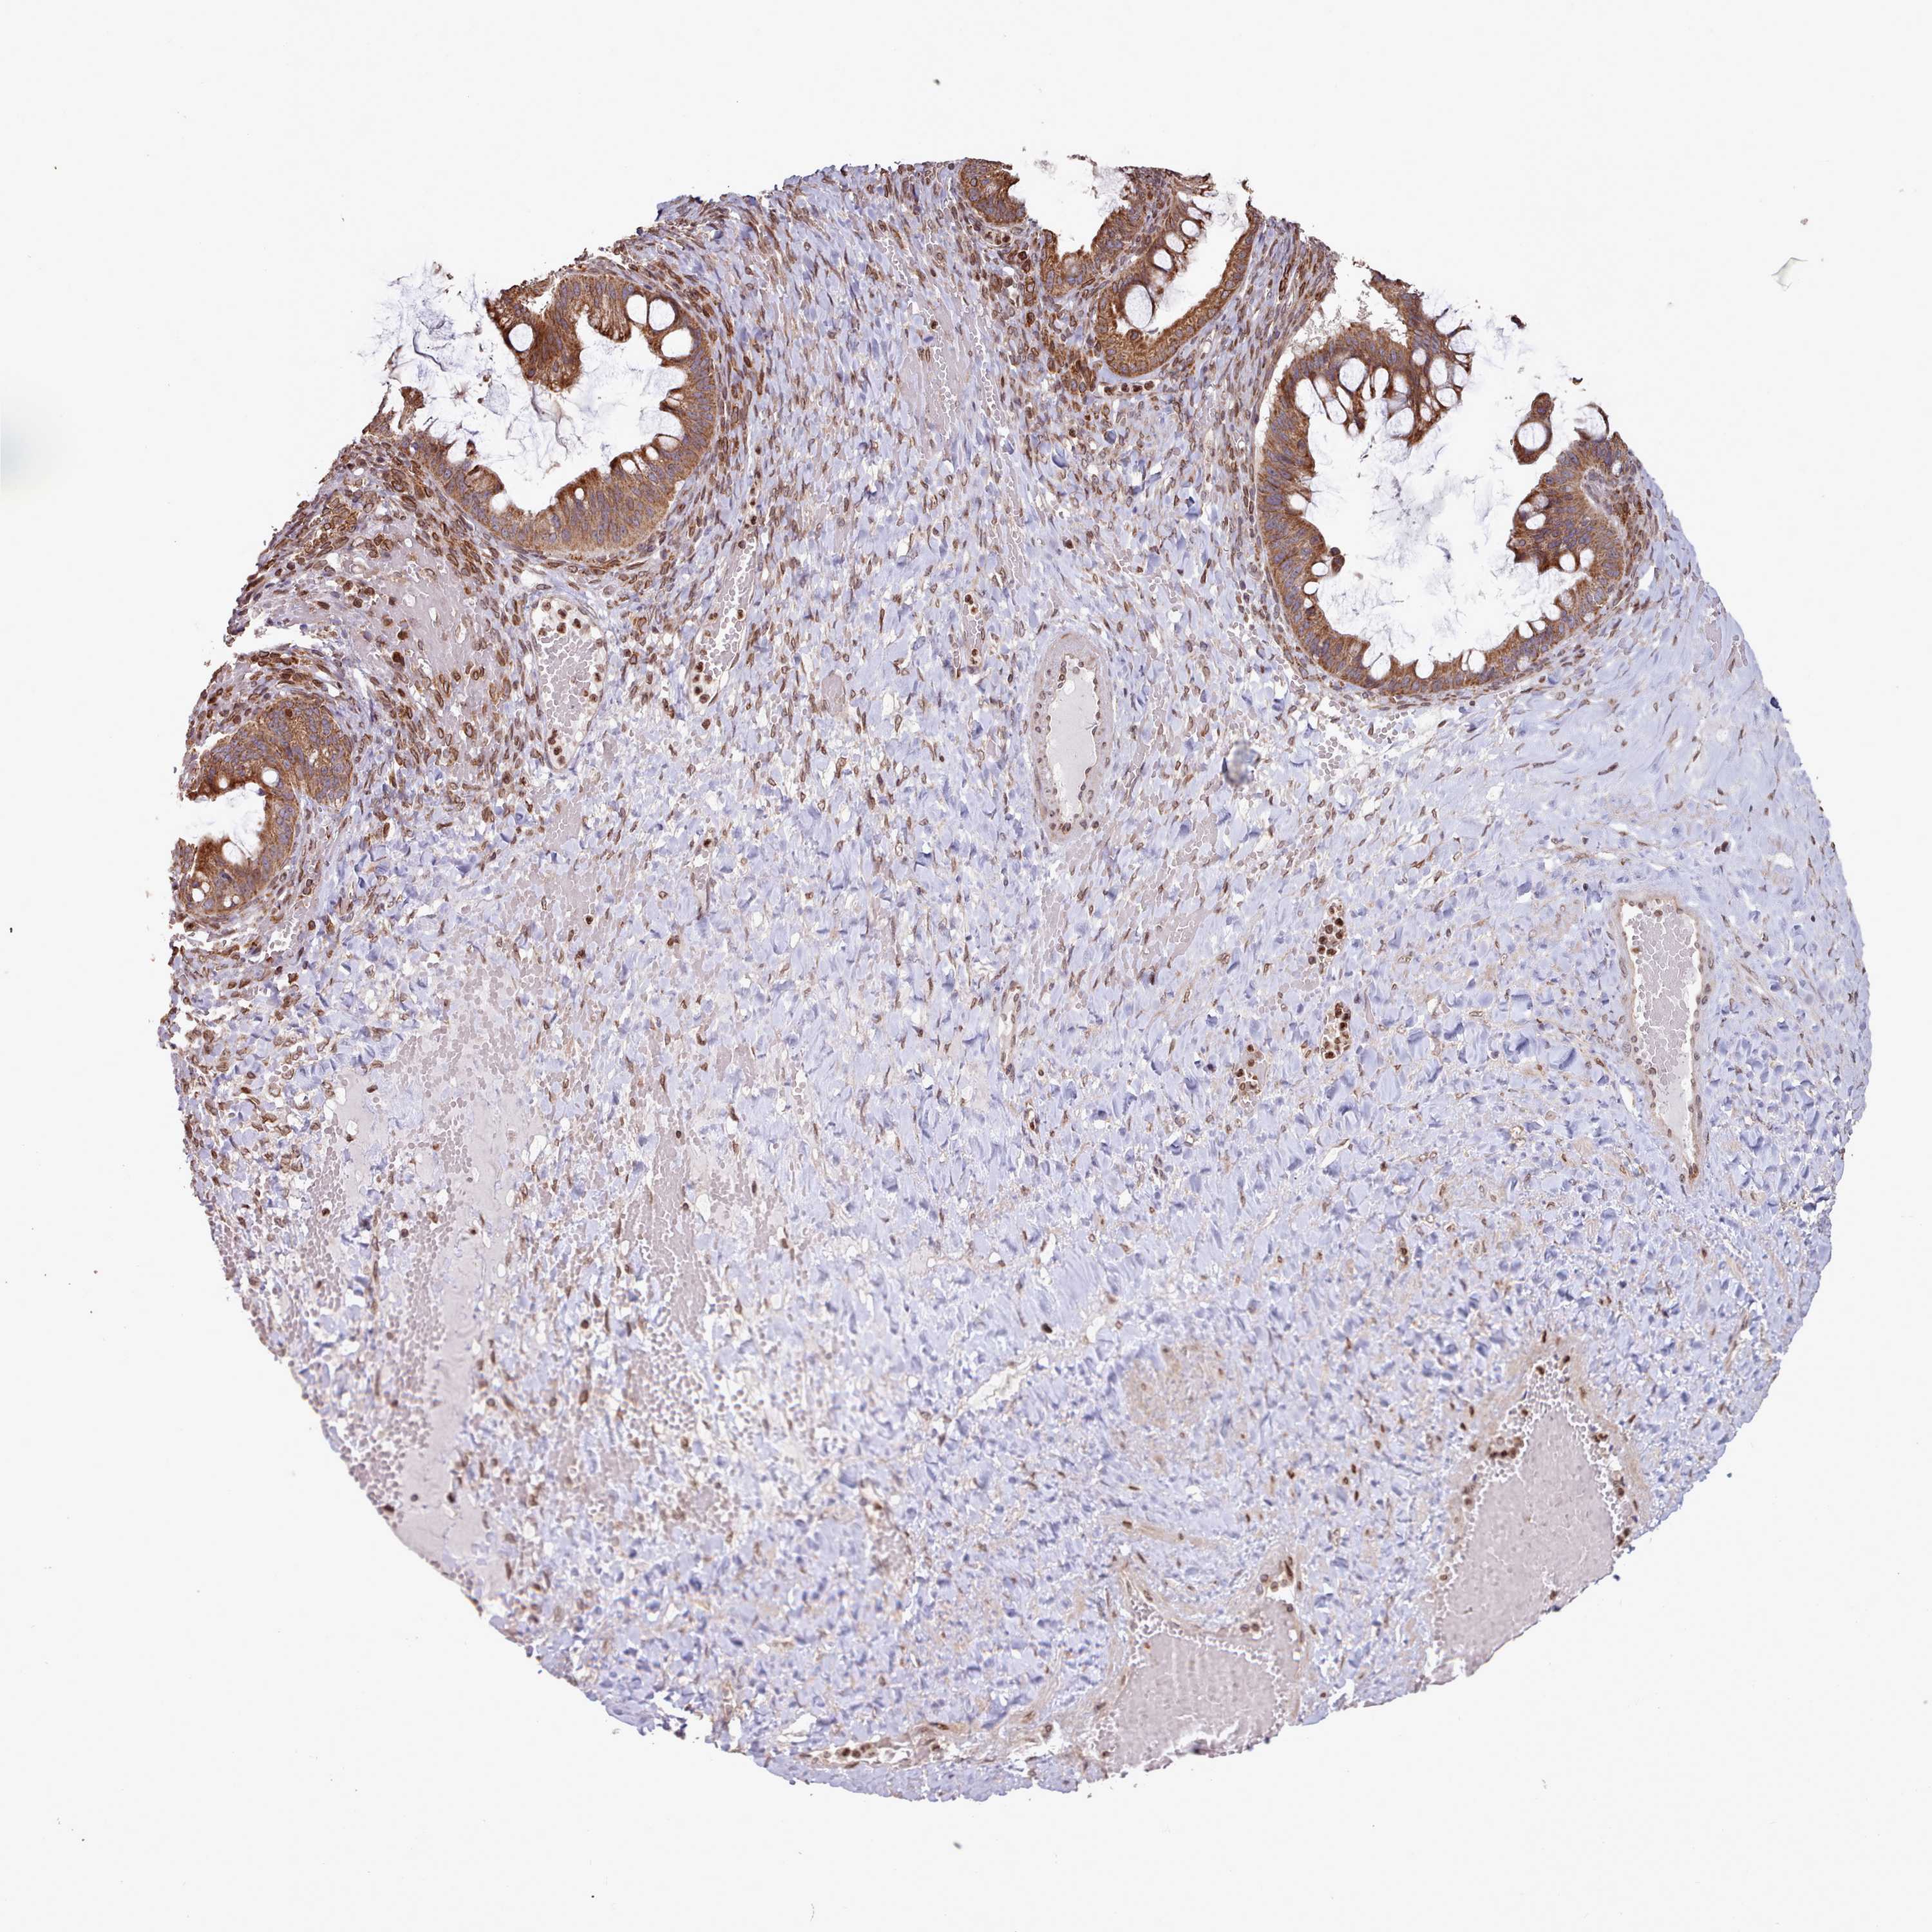

OVARIAN CANCER - Protein expressioni

A mouse-over function shows sample information and annotation data. Click on an image to view it in a full screen mode. Samples can be filtered based on level of antibody staining by selecting one or several of the following categories: high, medium, low and not detected. The assay and annotation is described here.

Note that samples used for immunohistochemistry by the Human Protein Atlas do not correspond to samples in the TCGA dataset.

Antibody stainingi

Antibody staining in the annotated cell types in the current human tissue is reported as not detected, low, medium, or high, based on conventional immunohistochemistry profiling in selected tissues. This score is based on the combination of the staining intensity and fraction of stained cells.

Each image is clickable and will lead to virtual microscopy that enables deeper exploration of all samples and also displays staining intensity scores, fraction scores and subcellular localization as well as patient and tissue information for each sample.

Antibody HPA047151

Cystadenocarcinoma, serous, NOS

Carcinoma, endometroid

Cystadenocarcinoma, mucinous, NOS

Carcinoma, NOS